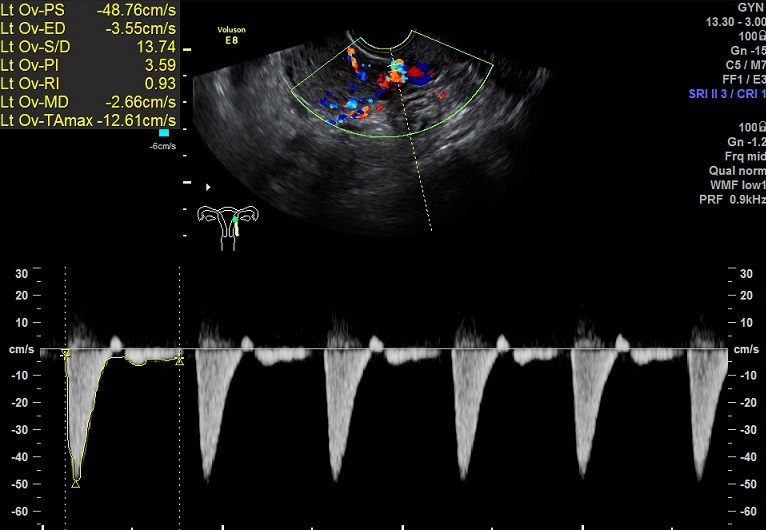

| 女性,25岁,继发性不孕1年余,难免流产4次。 | ||

2015-1-26 月经第23天检查 黄体期 |

2015-1-26图示